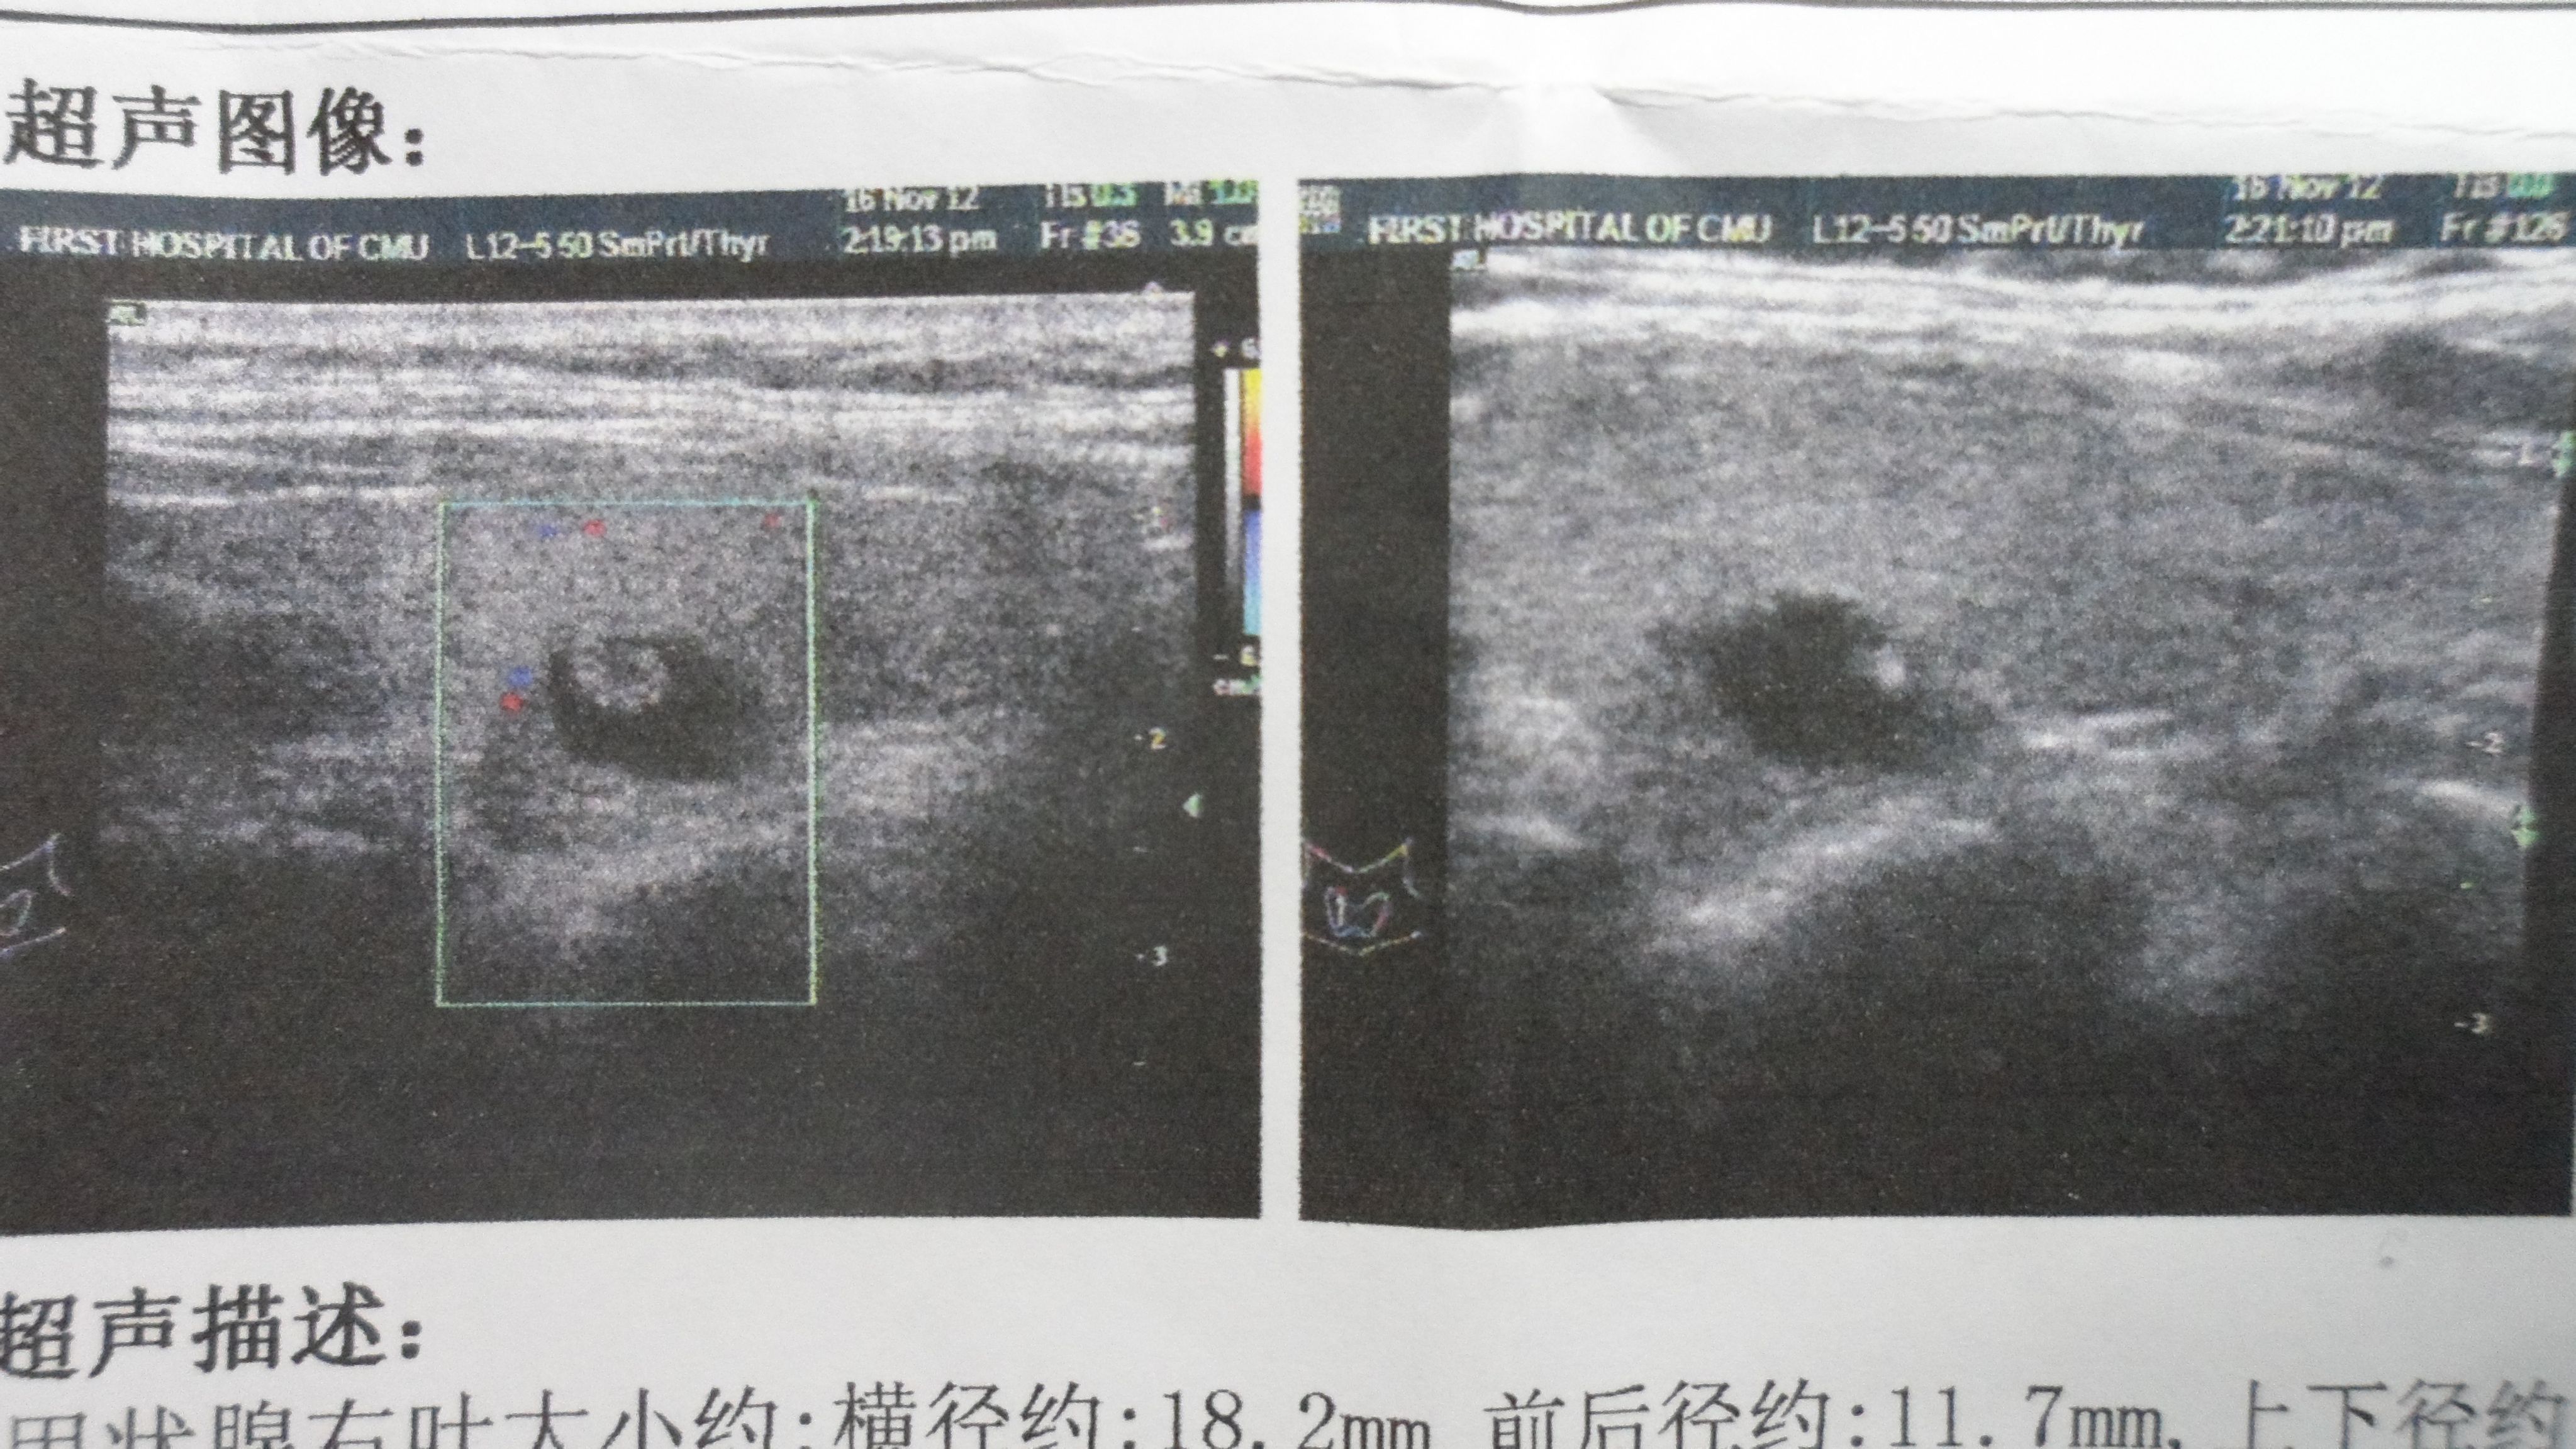

第一部分是图像。这部分主要是供超声医生参考的。

今天重点介绍图像显示的回声区域:

强回声,基本上就是钙化,钙化又分为粗大型钙化和细小型钙化,如果结果上显示出现钙化,这时候它的恶性程度会增高;

低回声表明它是一个实性的结节,根据其他相关描述,比如血流信号、形态、密度等,进一步判断是否为恶性;

无回声属于囊性结节,这种情况恶性程度是比较低的,你明白了吗?